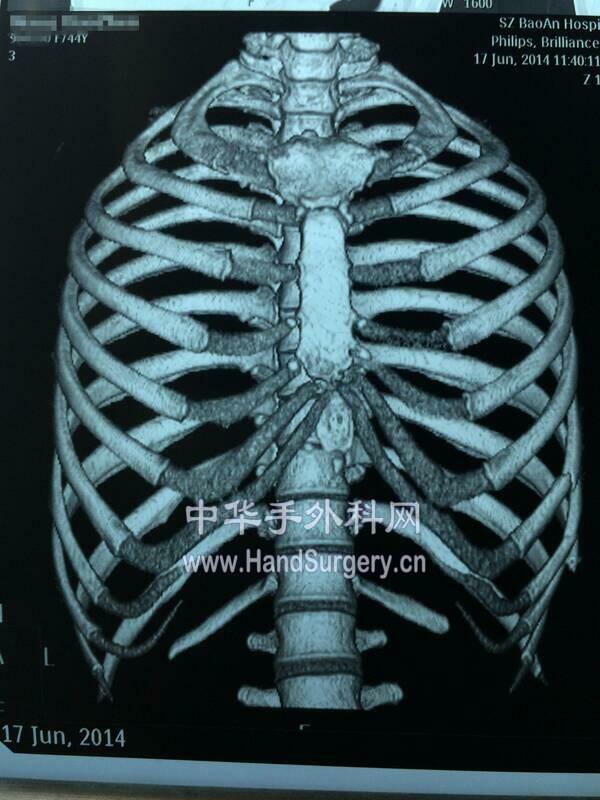

楼主| 发表于 2019-3-18 20:21:15 | 显示全部楼层

本帖最后由 zhangwenlong 于 2019-3-19 13:58 编辑

一般取第5.6.7肋

肋骨骨质与软骨很容易滑脱分离

雕刻时需要格外谨慎

可以用磨钻磨削骨质

不能磨削软骨

因为会造成软骨坏死

软骨可以用尖刀削剥